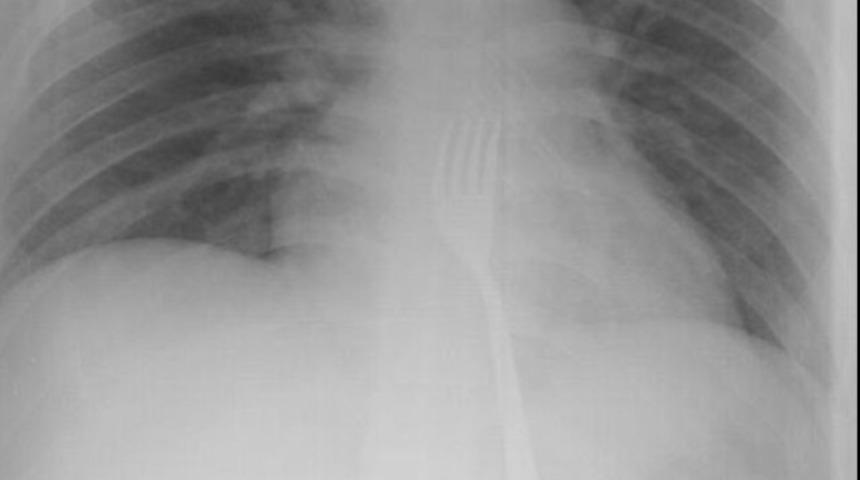

Çeşitli sağlık problemleri olduğu belirtilen 20 yaşındaki O.A'nın çatal yuttuğunu fark eden ailesi, oğullarını Necmettin Erbakan Üniversitesi (NEÜ) Meram Tıp Fakültesi Hastanesine götürdü. Çekilen röntgen filmlerinde, çatalın midede olduğu görüldü. O.A'nın midesinden 15 santimetrelik metal çatal, başarılı operasyonla çıkarıldı. O.A, taburcu edildi.

Hastanenin Genel Cerrahi Anabilim Dalı Öğretim Üyesi Prof. Dr. Mehmet Erikoğlu, yaptığı açıklamada, O.A'nın acil servise başvurarak, çatal yuttuğunu söylediğini anlattı. Kontrollerde çatalın yemek borusunun sonuna kadar inip midede kaldığını gördüklerini aktaran Erikoğlu, büyük olması nedeniyle çatalı operasyonla mideden küçük kesiyle çıkardıklarını ifade etti. Küçük bazı yabancı cisimlerin mideden atılabildiğini anlatan Erikoğlu, "Yabancı cisim düz yutulmuş olsaydı, ciddi sıkıntılar doğabilirdi. Çatal tersten yutulduğu için vücuda bir zararı olmamış. Bugüne kadar çatal yutmasıyla ilk kez karşılaştık." diye konuştu. Erikoğlu, yabancı cisimlerin vücuda vereceği zararın büyük olabileceğini, ailelerin özellikle bu konularda dikkat etmesi gerektiği uyarısında bulundu.